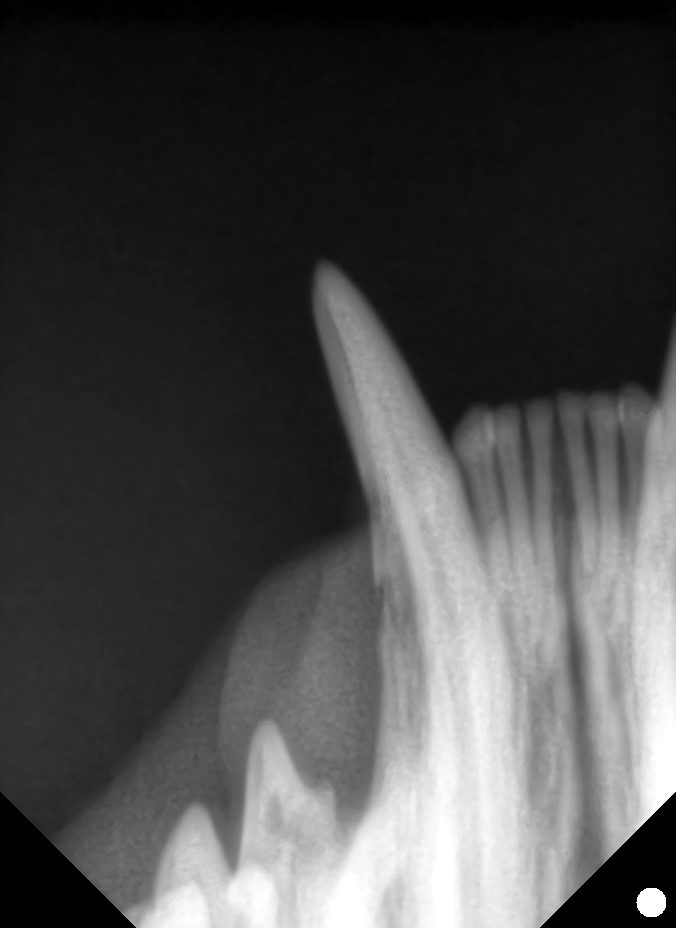

下の写真を見てみましょう。

左下顎の犬歯に特徴的な赤桃色の肉芽組織が被さっています。

歯科用レントゲンで確認すると、歯冠の吸収が起きており、破歯細胞性吸収病巣と診断しました。

隣の健康な歯と比べると分かるように虫食い状に歯が溶けてしまっています。

この症例の歯はStage2の吸収像が見られました。

この症例は写真左側の歯根はType1の治療を選択しました。